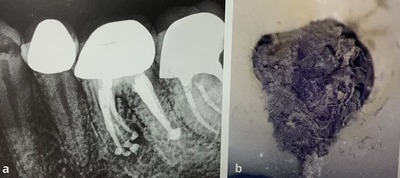

5本の神経をバッチリと詰めたのに、

中に入れた綿を取り忘れて治らなっかそうです。

右がその汚れた綿です。

結局,全部をやり直されたと。